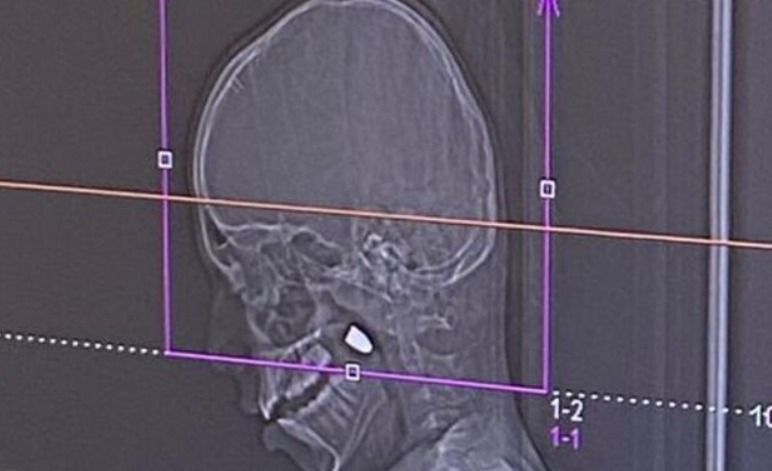

أطباء جراحون في مستشفى رمبام في حيفا أجروا أمس (الإثنين) عملية جراحية معقدة لاستخراج رصاصة أصابت رأس طفل يبلغ من العمر 11 عاماً، من سكان قرية مجد الكروم، والذي أصيب في ليلة رأس السنة الميلادية الجديدة. الحادثة وقعت عندما صعد الطفل إلى سطح منزله لمشاهدة الألعاب النارية التي أُطلقت كجزء من احتفالات د...